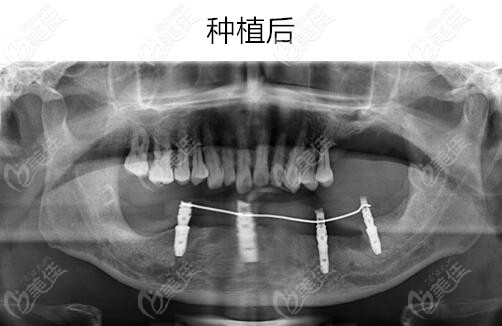

醫(yī)生介紹:王道軍,寧波牙博士口腔醫(yī)院院長(zhǎng)、主任醫(yī)師,從事口腔醫(yī)學(xué)研究和臨床工作23年,曾多次進(jìn)修于南京口腔醫(yī)院和韓國(guó)交流學(xué)習(xí)口腔種植技術(shù),積累了扎實(shí)的口腔醫(yī)學(xué)理論基礎(chǔ)和豐富的臨床手術(shù)經(jīng)驗(yàn)。王道軍院長(zhǎng)熟練掌握多個(gè)種植系統(tǒng)的種植技術(shù)、系統(tǒng)、全面地理解口腔種植專(zhuān)業(yè),把握親的種植牙發(fā)展方向與理念,熟練掌握先進(jìn)種植外科技術(shù)并應(yīng)用于臨床,已...